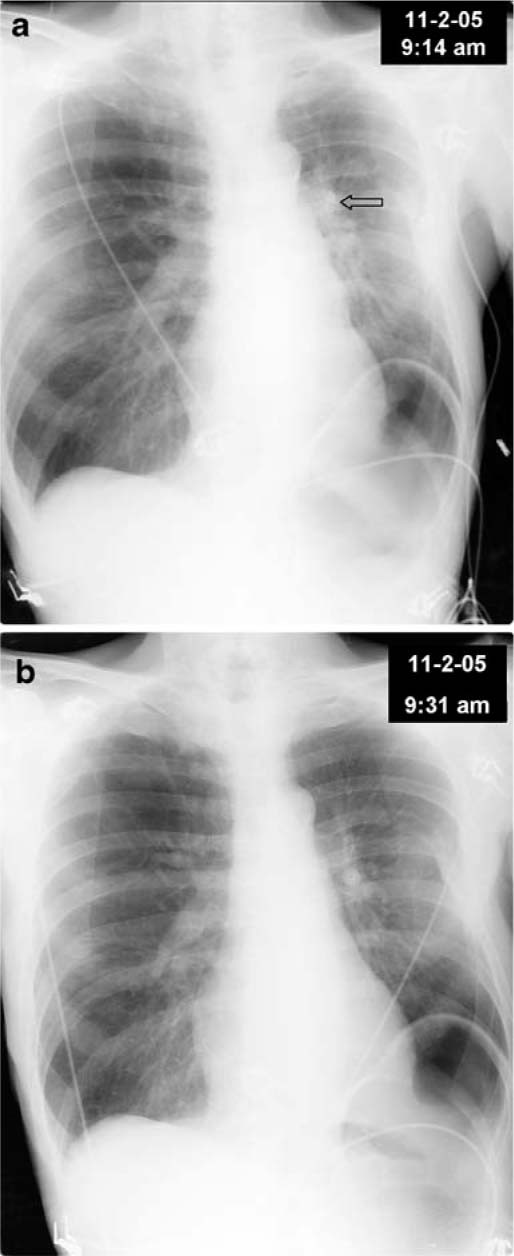

A 61-year-old man presented to the emergency department (ED) with sudden onset shortness of breath, coughing paroxysms, and a brief loss of consciousness. The emergency medical services (EMS) noted the patient to be diaphoretic and unresponsive, with a prior history of single lung transplantation. His current medications were multiple, without known allergy. Upon ED arrival, the patient was alert and oriented with normal vital signs, except for a marked tachypnea and saturations of 64% on 100% oxygen via a non-rebreather face mask. The initial chest radiograph shows a density in the left upper lung field, missed on the radiologist’s reading of the film (Fig. 1a, arrow). Shortly thereafter, the patient began to cough violently and expelled a large pellet of chalk-like material, ascertained to be the remnants of a calcium supplement. Post expulsion, the oxygen saturation immediately rose to 99% and his respiratory rate decreased to 14. A repeat chest radiograph revealed an absence of the calcified density in the left upper lobe, and clear reduction of adjacent parenchymal atelectasis (Fig. 1b). Clinicians should consider the possibility of pill aspiration on the differential for sudden marked hypoxia and tachypnea, especially in post lung transplant patients.